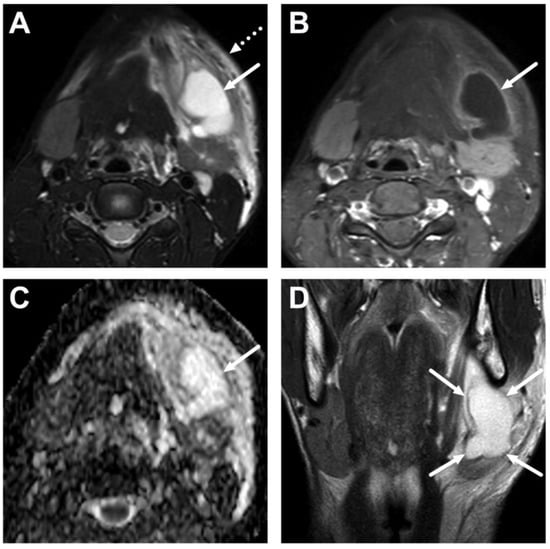

4.1. Tonsillitis, Peritonsillar Abscesses, and Parapharyngeal Abscesses

4.2. Retropharyngeal Abscesses and Suppurative Lymphadenitis

| Abscess | T1 SE T2 Dixon (water) DWI post-contrast T1 Dixon (water) | Non-enhancing collection with low ADC values enclosed in abnormally enhancing soft tissue edema. | Detection of an abscess usually requires operative consideration and exact abscess location, and extensions are useful in operative planning. | Abscesses may have an intermediate T2 signal content; blood products and/or postoperative status may complicate abscess assessment; necrotic lymph nodes may be misinterpreted as suppurative lymphadenitis. |